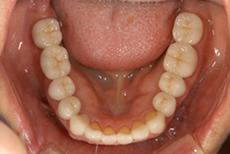

審美的で健康にも良い セラミックスでの治療はこんな感じです。 |

かぶせ物にはオールセラミック治療

治療費は高くなってしまいますが、やるならばオールセラミック治療を提案することが多いです。

なぜならば、審美的に最も優れているからです。

天然の歯のような美しさを出すことができます。

前から数えて4番目、5番目の歯、つまり、笑った時にギリギリ見える歯は審美領域になるのです。つまり、その人の印象を大きく左右する部分になります。

ですから、少なくとも4番目、5番目の歯はかぶせ物の場合、オールセラミック治療をされることをオススメします。ただし、治療費の関係で難しい場合にはメタルボンド(従来型のセラミック治療)を提案します。